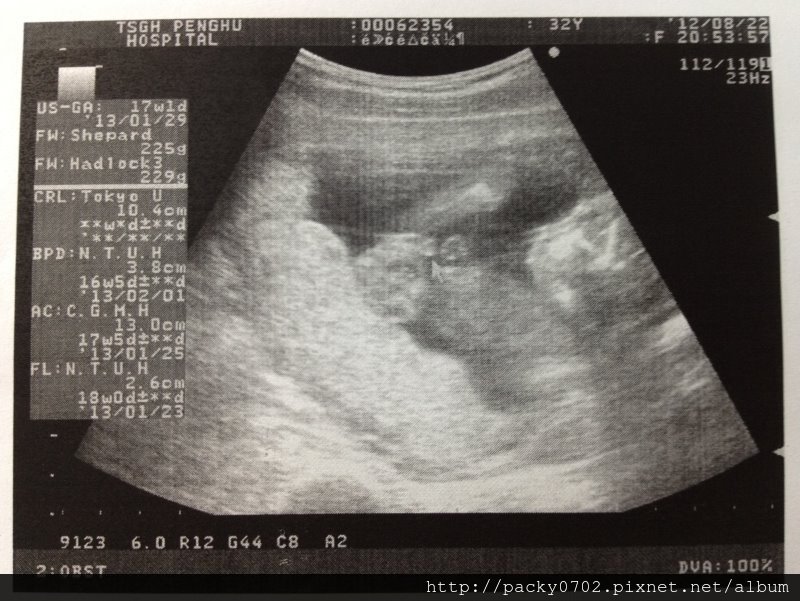

超音波檢查,醫生說道寶寶的手臂腿骨都很長、脊椎也是完整的,

有沒有有沒有?脊椎連貫的喔~

20120822 (8)

有沒有?很長的腿骨吧?

20120822產檢影片